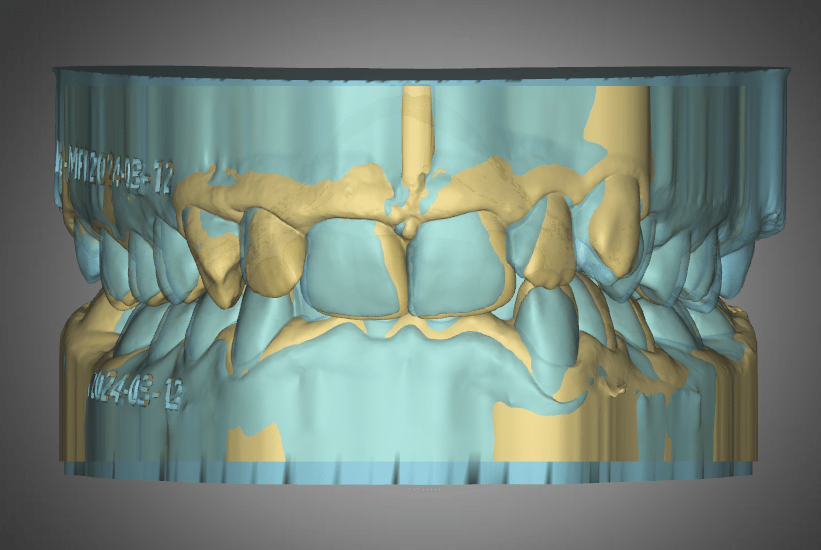

Mackenzie. L – Myobrace – Age 9

Adaptive Orthodontics TREATMENT STARTED AT AGE : 9 Myobrace K1 MediumMixed DentitionClass 2 Div IModerate 1st Review – 2023-03-01 YELLOW = Initial 2022-10-29 BLUE = 1st Review 2023-03-01 Compliance was not good in the first quarter. Not much expansion seen on buccal side 2nd Review – 2023-05-30 YELLOW = Initial 2022-10-29 BLUE = 2nd Review2023-05-30… Read.